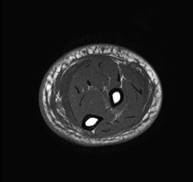

- Thigh MRI

Ideal examination for studying injuries to the hamstrings and quadriceps, which are frequently injured in athletes. It also allows for a good assessment of tendons and peripheral nerves. It lasts approximately 20 minutes. It is a radiation-free procedure.